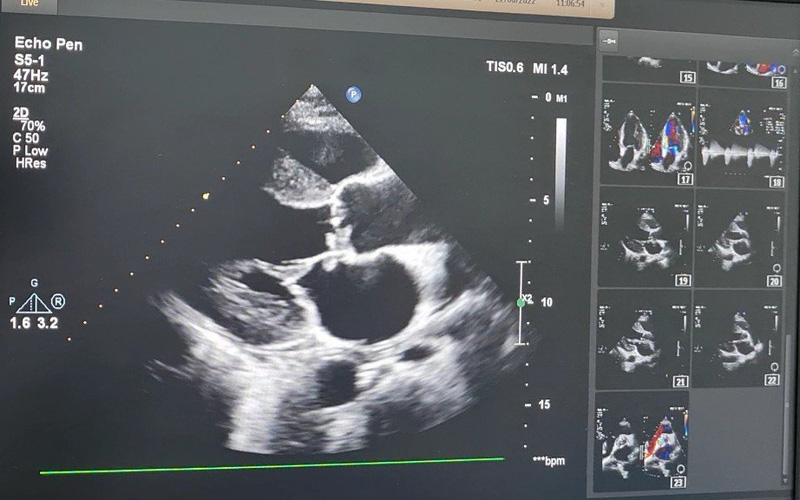

Một trường hợp khác là bệnh nhân N.V. D. (55 tuổi, Hải Phòng), nhập viện trong tình trạng khó thở dữ dội, đau ngực trái kèm sốt cao, suy kiệt, tự điều trị tại nhà không đỡ. Kết quả xét nghiệm cho thấy bệnh nhân bị nhiễm vi khuẩn Streptococcus oralis trong máu. Siêu âm tim cho thấy tình trạng sùi loét thủng 2 van tim. Bác sĩ khoa Hồi sức tim mạch nhanh chóng chẩn đoán đây là trường hợp bị nhiễm trùng máu nặng, nhiễm trùng lan tới cả van tim. Được biết trước đó, bệnh nhân bị đau khớp gối và đau lưng, đã được bác sĩ tư nhân tiêm Corticoid trực tiếp vào khớp gối và cột sống thắt lưng. Mặc dù triệu chứng đau khớp có đỡ, nhưng sau khi tiêm khớp được 2 ngày, bệnh nhân bị sốt triền miên, mệt mỏi và khó thở liên tục.